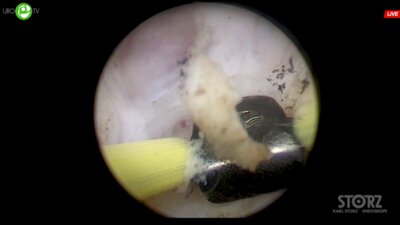

Uro.TV

Сорокин Николай Иванович

д.м.н., профессор, руководитель урологической службы МНОЦ МГУ, ведущий научный сотрудник ФФМ МГУ им М.В. Ломоносова